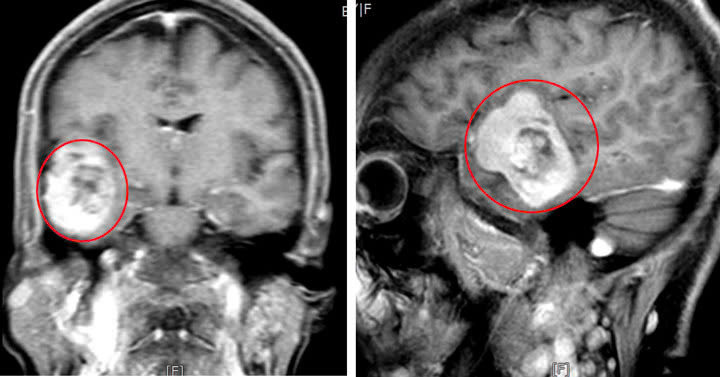

| Hình ảnh khối u của người bệnh. Ảnh BVCC |

Sau khi thăm khám và chụp cắt lớp vi tính, MRI phát hiện có khối u màng não lớn kích thước 5x4cm, khối u nằm ở vùng hố thái dương dính vào màng cứng. Các bác sĩ đã nhanh chóng tiến hành phẫu thuật vi phẫu bóc tách và loại bỏ khối u.